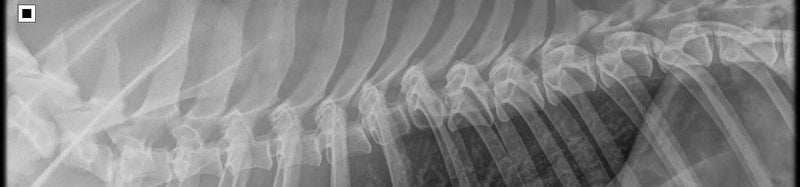

Röntgen foto van de rug,

Ruggenmerg niks gevonden en heeft een goede doorstroming.

Geen spondylose.

Geen verkalkingen over de hele wervelkolom.

Röntgenfoto Vlinder